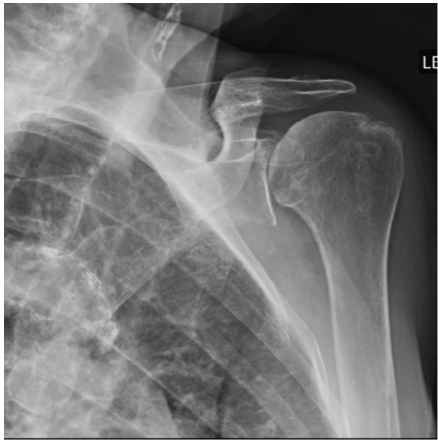

A 70-year-old woman with chronic left shoulder pain and weakness presented to our clinic and was diagnosed with rotator cuff arthropathy (Fig. 1).

Figure 1: A pre-operative Grashey view radiograph of the left shoulder.